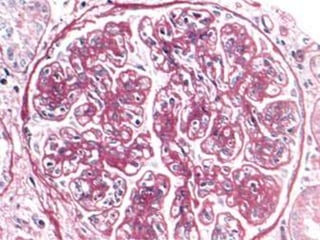

   Tamaño y Estructura de los glomérulos se

encuentran: NORMALES.

Denominada enfermedad: Nula Nefritis Lipoidea Enfermedad de Podocitos  Tamaño y Estructura de los glomérulos se encuentran: NORMALES.

No existe deposito de: C3 Hipercelularidad Ig Mesangial, Depósito de C3 – Ig G: PEOR PRONOSTICO Microscopio Electrónico Borramiento Difuso y característico de Podocitos de células del Epitelio Visceral